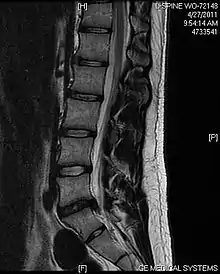

L'imagerie par résonance magnétique peut montrer la hernie, le canal vertébral, les nerfs, les tissus environnants. Les tissus mous sont les mieux analysés par cet examen qui est le plus performant pour le diagnostic de hernie discale. Les images pondérées en T2 montrent clairement la hernie.

IRM cervicale sagittale montrant une hernie discale de niveau C5-C6. IRM cervicale sagittale montrant une hernie discale de niveau C5-C6.